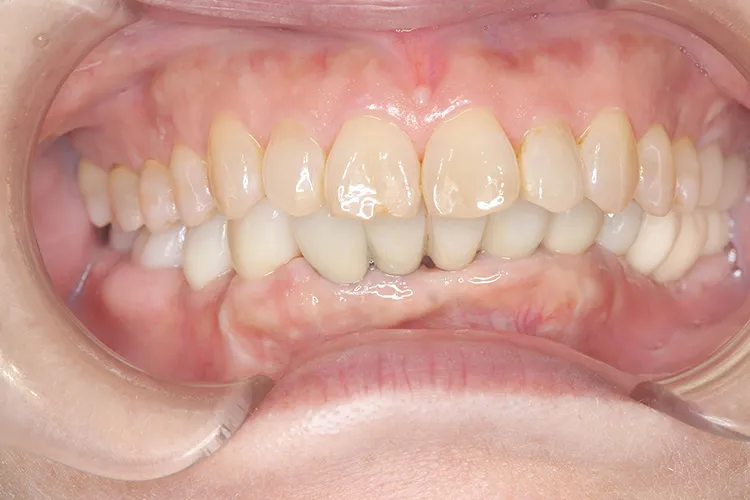

歯ぎしり・食いしばりが強い方の治療ケースです。全体的に歯が擦り減り正面から見て下の歯が見えないほど噛み合わせの高さが失われており、顎関節にも症状がでていました。ヒビが入って保存不可の歯を抜歯しインプラントを計5本埋入し、前歯・臼歯にインプラント土台のブリッジを入れることで噛み合わせの高さを回復しました。古い金属の被せ物もジルコニアでやりかえました。噛み合わせの高さが改善したことで顎関節症状もなくなり快適に過ごされています。歯ぎしりがある方は、夜間のナイトガード装着が必要になります。